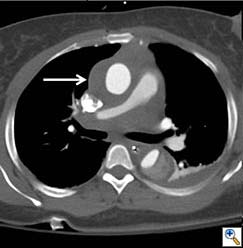

A 49-year-old woman with a history of hypertension and smoking presented to an outside hospital with sudden onset chest pain and hypotension. Computed Tomography/ Angiography (CTA) of the chest and abdomen revealed a type A aortic dissection extending from the ascending aorta to the left common iliac artery. (Figure 1) Of note, there was a significant pericardial effusion and left pleural effusion. Due to her hypotension and tamponade physiology, the patient was rapidly intubated followed by unsuccessful pericardiocentesis. The patient was then transferred to our institution for emergent dissection repair.

Figure 1a-e. Computed Tomography/Angiography (CTA) at

presentation demonstrating a type A aortic dissection.

Figure 1a. Axial CT at level of the pulmonary artery. The false lumen in the ascending aorta (white arrow) has minimal flow.

Figures 1b-d. Axial CT cuts demonstrating the dissection continuing into the left common iliac artery.

Figure 1e. Oblique sagittal CT reconstruction demonstrates the Type A dissection is complex with multiple fenestrations in the abdomen. Note bovine arch anatomy.